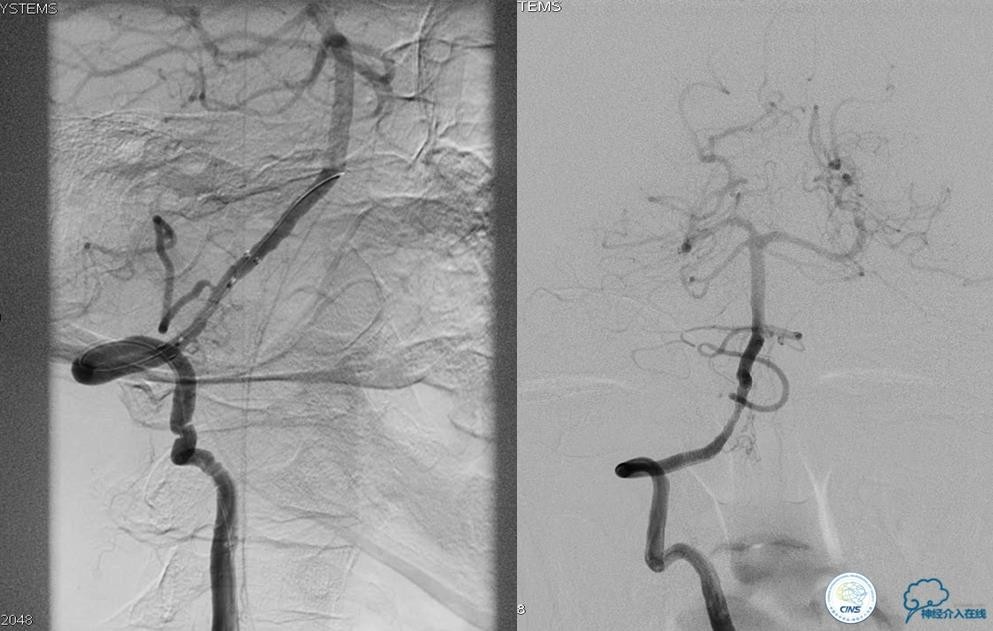

▼开通

出院情况:头晕症状消失,构音障碍缓解,进食无呛咳,饮水实验(-),右侧肢体远端肌力恢复到Ⅰ级。